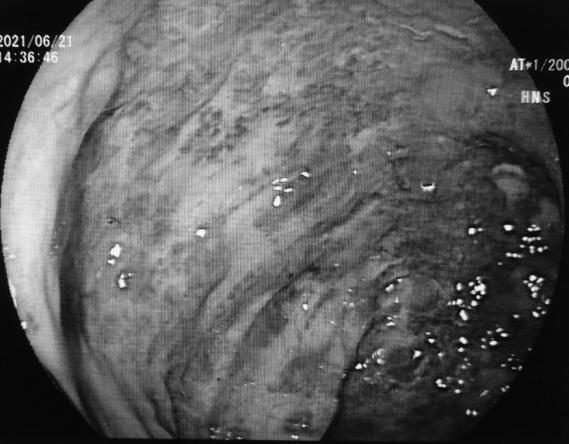

患者术前和术后内镜对比

术前内镜下直肠曲张静脉